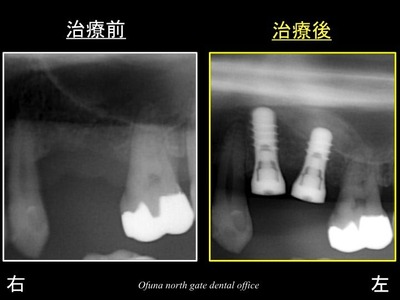

治療前後を比較してみましょう!

以下の左側が治療前

右側が治療直後です。

移植した人工骨により上顎洞の位置が上方に挙上されているのが分かります。

骨の高さが少ない場合には、このようにソケットリフト法 を行うことによりインプラントの埋め込みが可能となるのです。